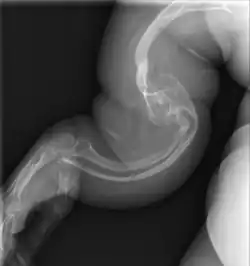

Les aspects radiographiques de l'os contribuent au diagnostic.

Diagnostic radiologique

On observe une transparence excessive des os ainsi que des déformations sur les clichés radiologiques[7]. Ces déformations sont principalement constatées au niveau de :

- la partie diaphysaire de l’os : une corticale diaphysaire mince, une crosse au niveau des os longs ainsi que la présence de plusieurs cals osseux ;

- la hanche avec une protrusion acétabulaire c'est-à-dire une malformation associant une hanche trop profonde et des amplitudes articulaires diminuées ;

- des pieds avec des pieds plats et en valgus c'est-à-dire les membres qui s’écartent vers l’extérieur par rapport à l’axe du corps ;

- des membres supérieurs avec une déformation supérieur à 30° ;

- du crâne avec des os wormiens c'est-à-dire des petits os situés à l'intérieur de divers os constituant le crâne (occiput, pariétal, temporal…) présents en nombre plus important que la normale ;

- du rachis et du thorax avec un thorax plus bombé que la normal et des modifications au niveau des vertèbres telles que des tassements de certaines vertèbres, des vertèbres biconcaves, des scolioses… Lors de fractures, le siège se situe principalement au niveau des membres inférieurs et des vertèbres.